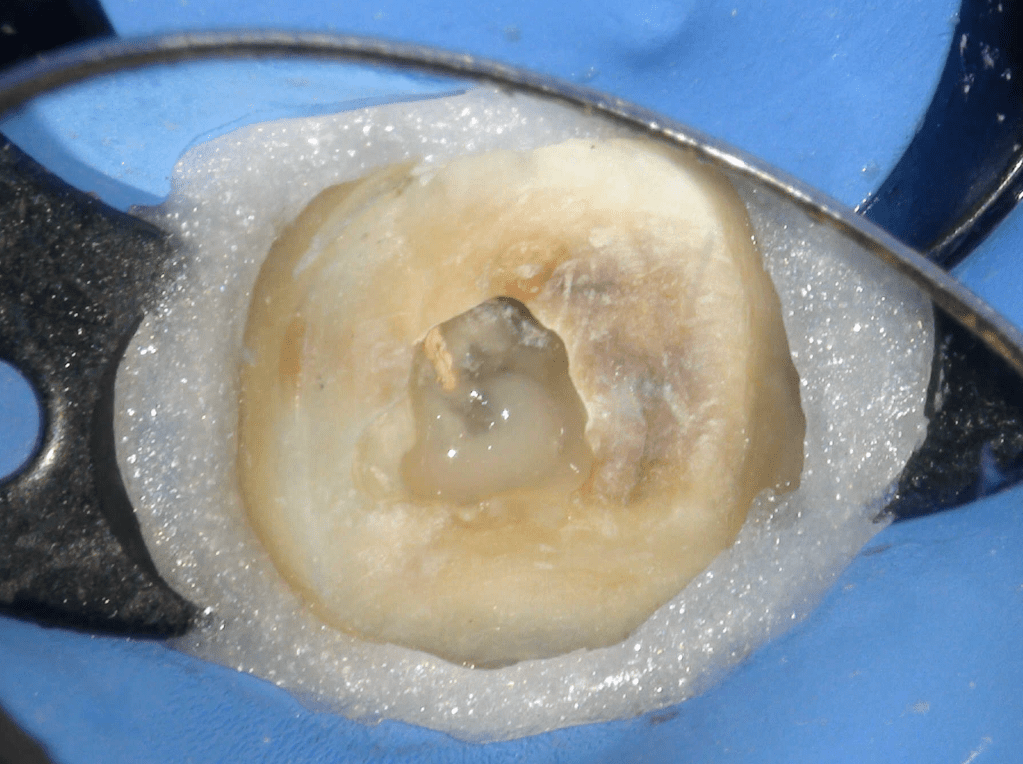

Molar superior

Reco preendo + 4 conductos molar superior